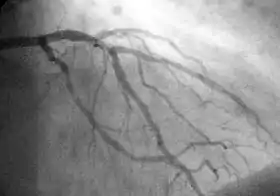

A coronary angiogram showing the circulation in the left main coronary artery and its branches.